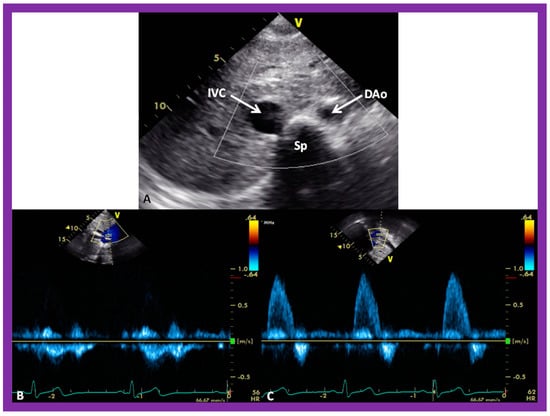

A predictable relationship between the locations of the aorta (Ao) and the IVC at the level of the diaphragm with the atrial situs seems to exist [4,5,30]. The location of the IVC and Ao at the level of the diaphragm can easily be imaged on short-axis echo views (Figure 26A). The IVC is typically larger than the Ao (Figure 26A). In addition, the Doppler flow patterns with the venous flow for the IVC (Figure 26B) and arterial flow for the Ao (Figure 26C) confirm the identity of the respective vessel.

Figure 26. Selected video images secured in a short axis echo view of a normal child, illustrating the positions of the aorta (Ao) on the left side of the spine (Sp) and the inferior vena cava (IVC) on the right side of the Sp. (A) The IVC is generally larger than the Ao. (B,C) demonstrate Doppler flow characteristics with low-velocity venous flow in the IVC (B) and a higher velocity arterial flow in the Ao (C). These data are indicative of situs solitus. Reproduced from reference [4].

In patients with situs solitus, the Ao is on the left of the spine, and the IVC is on the right of the spine (Figure 26). In subjects with situs inversus, the positions of the IVC and Ao are reversed, left to right, with the IVC on the left side and Ao on the right side. In subjects with dextro-isomerism (asplenia syndrome), the IVC and Ao are placed together on either the right or left side of the spine. The Ao is usually anterior to the IVC. In subjects with levo-isomerism (polysplenia syndrome), the Ao is typically in the midline, anterior to the spine, and the azygos vein is located behind the aorta. The location of the azygos vein is on the right of the spine in subjects with azygos continuation of the interrupted infrahepatic IVC, while its location is on the left side of the spine in subjects with hemiazygos continuation of the interrupted infrahepatic IVC. Consequently, the comparative locations of the Ao and IVC are valuable in the assessment of the atrial situs [4,5,30].